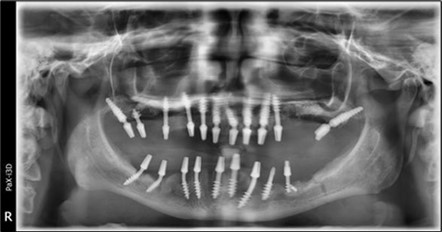

Figure 3.Panoramic pictures after removal of implants affected by peri-implantitis, extractions, alveolar crest regularization, and insertion of corticobasal and TPG implants (07.2022)

A total of 11 implants is placed in the maxilla, including compressive TPG implants with a polished surface in the maxillary-sphenoid fusion area (Figure 3, Figure 9). Similarly, in the anterior region, final fixation is achieved in the nasal cortex, and BCS corticobasal implants are added in areas with massive bone loss in the frontal region (Figure 3, Figure 8, Figure 11). Additionally, in the palatal sinus cortical area, with the aim of avoiding the addition and sinus lift zone where the second cortical bone no longer exists, 3 implants are placed, 2 in quadrant 1 and 1 in quadrant 2 (Figure 3, Figure 8). Through the Caldwell-Luc sinus lift procedure, the sinus cortical bone is displaced to allow the placement of the graft material and elevation of the sinus membrane. This sinus cortical is no longer recreated at the junction of the graft material and mucosa-sinus membrane, making it impossible to place a corticobasal implant, which relies on the second cortical bone. In the distal mandibular area, after the removal of two stage implants due to massive destruction in quadrant 3, implant placement distal to the mylohyoid line is not possible, as in quadrant 4 (Figure 10). A re-intervention occurs after 5 months to stabilize the area (Figure 12, Figure 14). Also, at the moment of fixation, the tip of one implant fractures, and the decision is made to leave it in place due to regional bone destruction, in order to avoid enlarging the bone defect.

In the interforaminal area (Figure 3, Figure 13), 6 corticobasal implants are also placed. The increased number of implants is due to the poorly represented distal area that needs to be compensated.